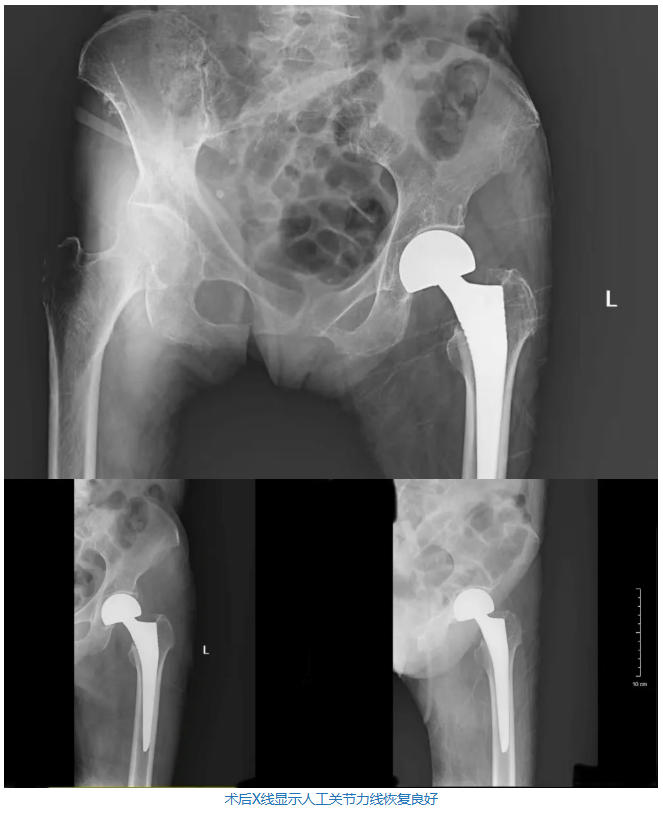

在这套“无痛组合拳”的保驾护航下,李锋教授与秦皇岛医院骨科团队默契配合,顺利取出了骨折的股骨头,并稳稳地植入了人工半髋假体,全程出血量极少。

最令人惊喜的是,王奶奶术后回到病房时,完全没有感受到传统骨科大手术后的剧烈疼痛!经医护人员评估,老人的术后疼痛评分(VAS评分)基本达到了0分(完全无痛)! 真正做到了让老人“不遭罪”,为术后的极早期下地活动和快速康复(ERAS)扫清了最大的障碍。